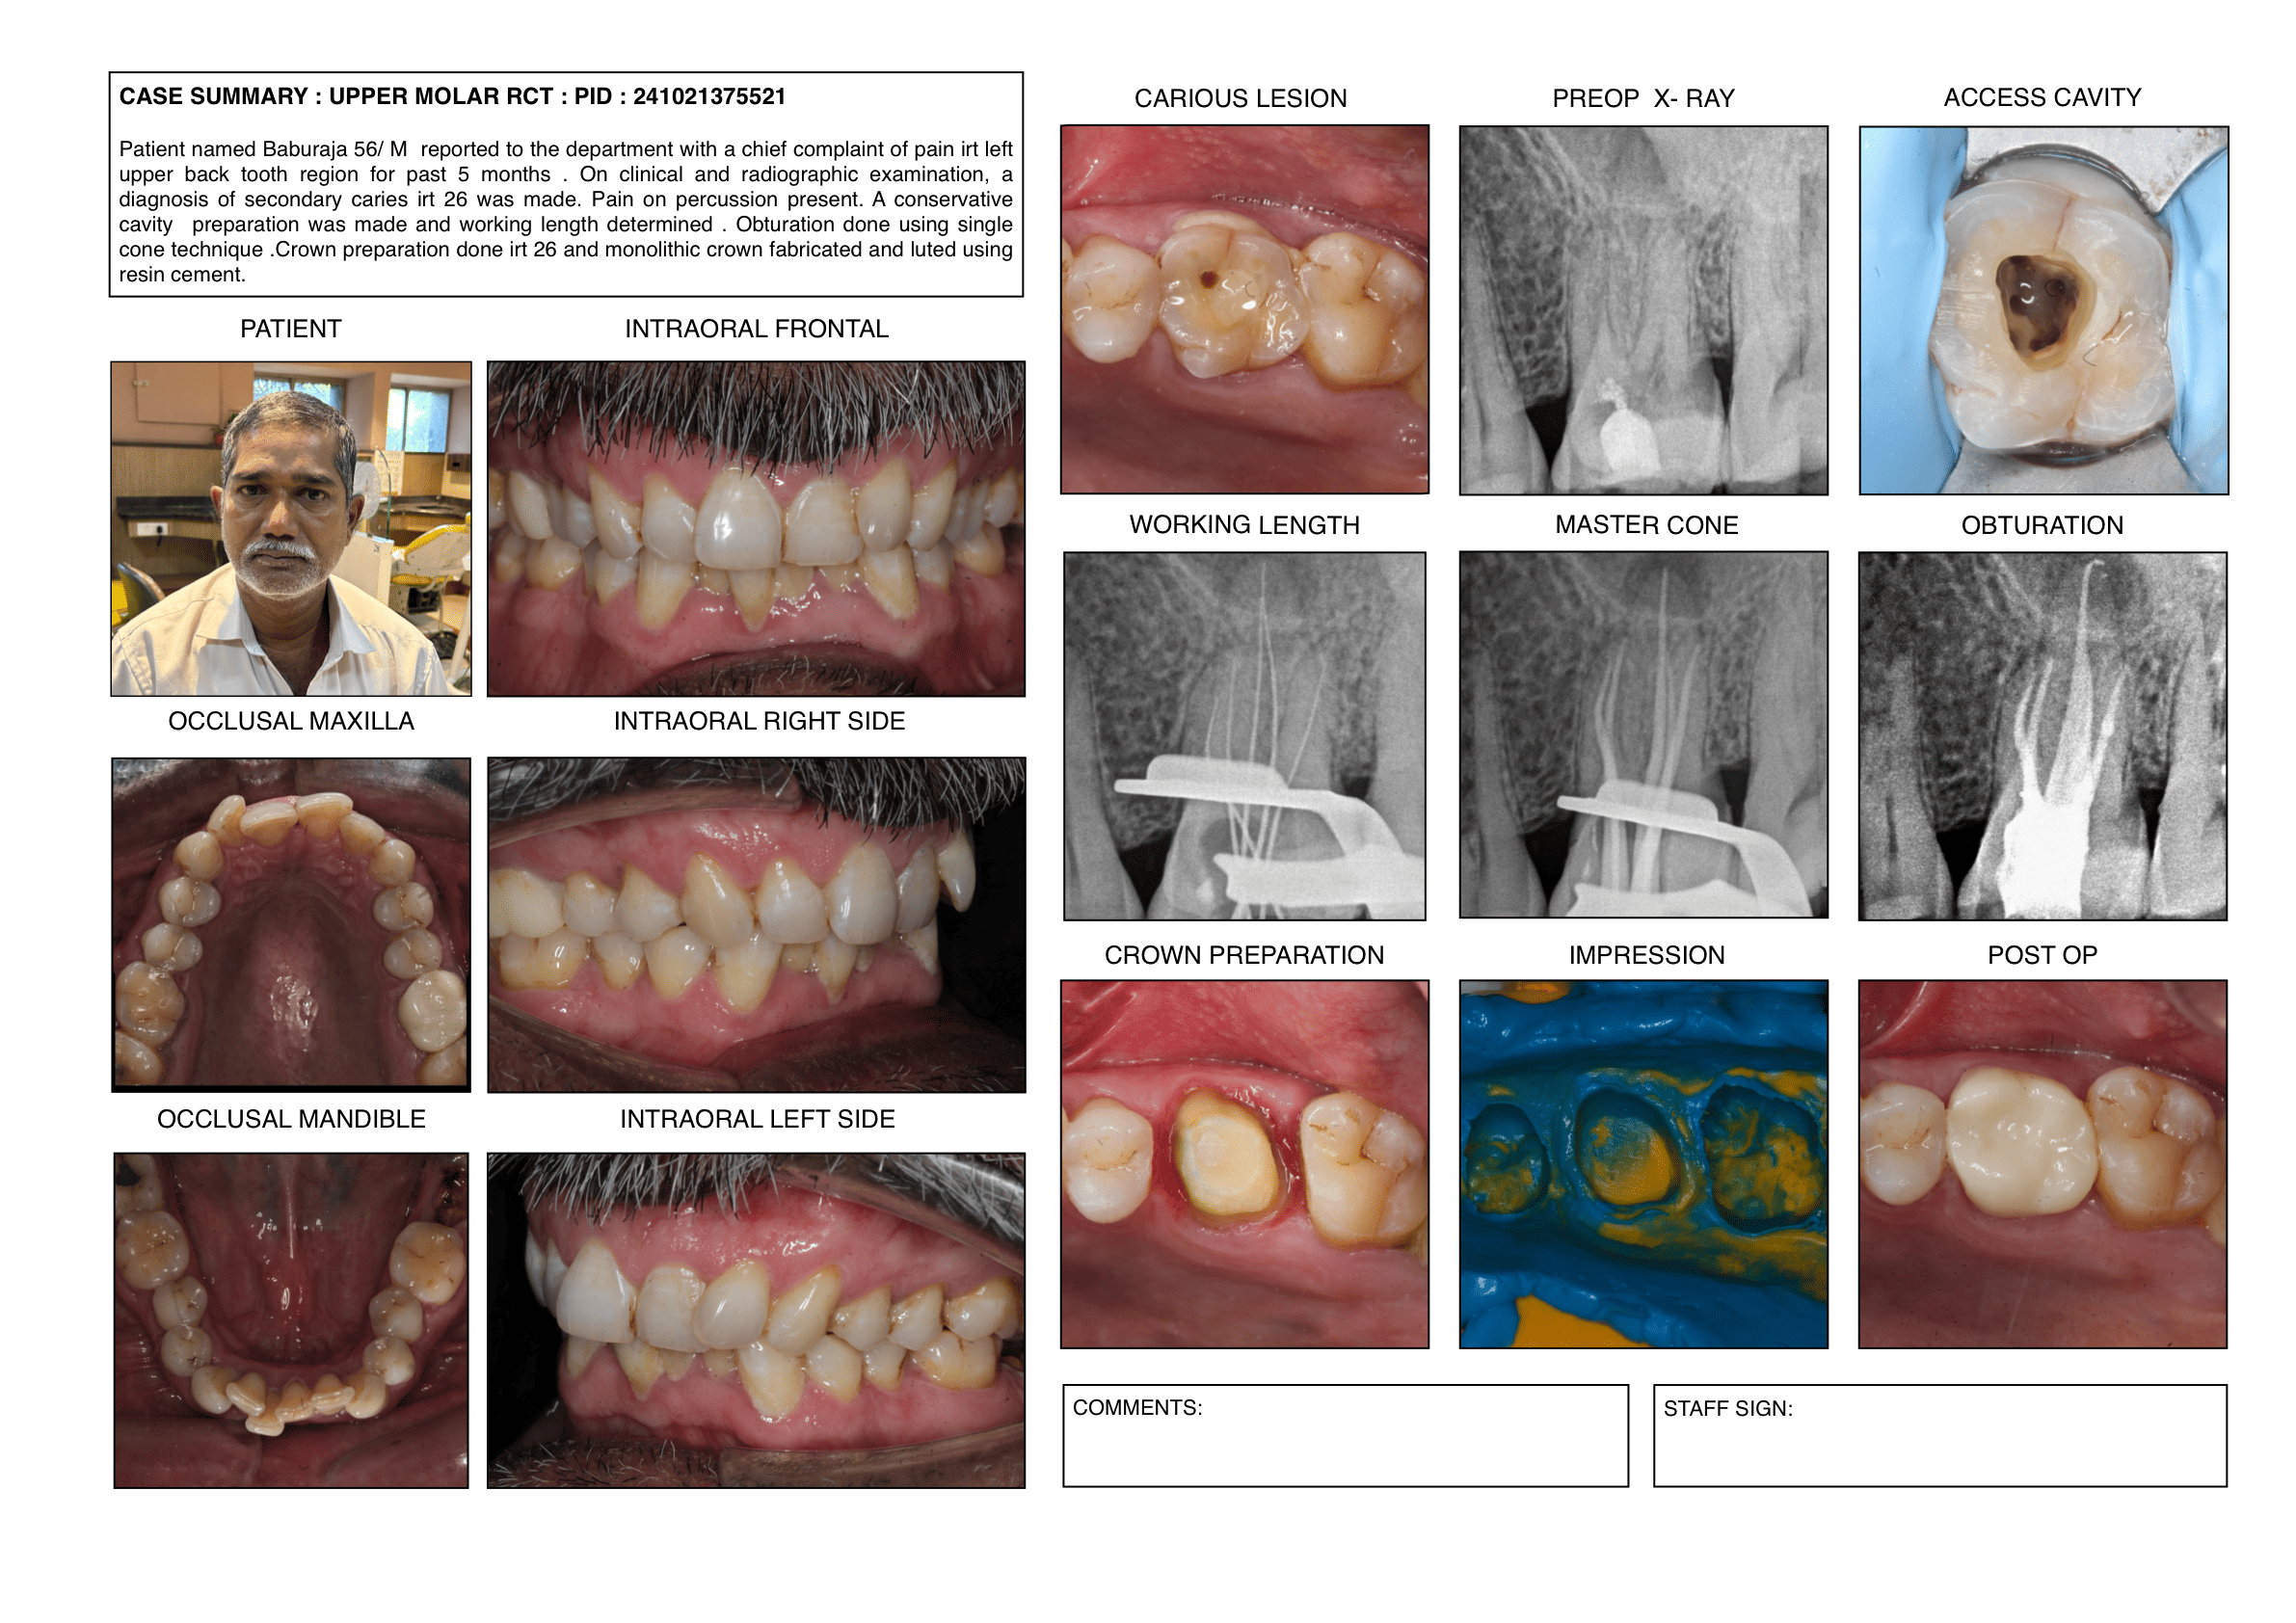

Endodontic cases